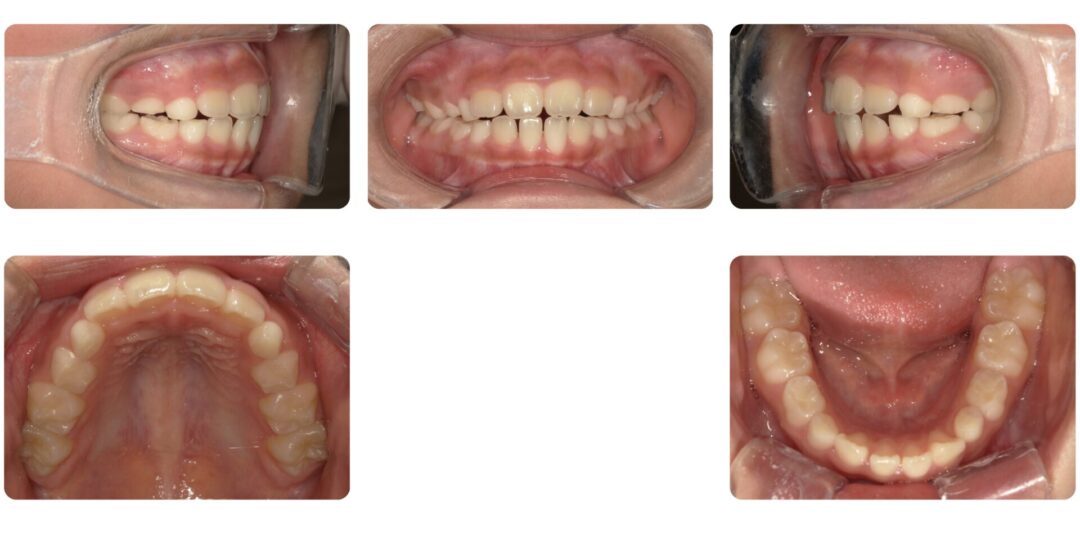

矯正治療後

治療内容

第一期治療 拡大床ネジ付きバイオネーターによる歯列矯正

治療期間

1年3ヶ月

治療費用

自由診療 基本料金¥330,000 処置料¥3,300